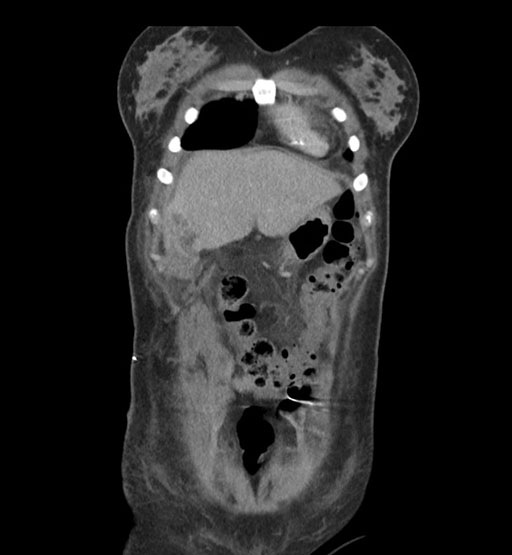

Imaging Analysis

Look through the patient's CT scan to identify any areas of concern for the necessary procedure.

Coronal Arterial

Based on initial findings, which issue(s) would you be most concerned about?